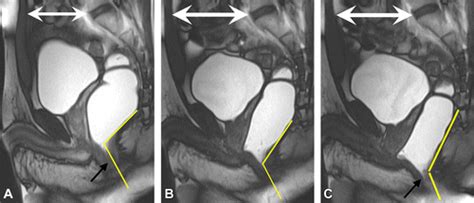

Diagnostika anomálií Müllerových vývodov sa zakladá predovšetkým na pacientových ťažkostiach a následnom gynekologickom vyšetrení. Kľúčovú úlohu zohráva ultrazvukové vyšetrenie a magnetická rezonancia (MRI).

V minulosti sa na diagnostiku používala hysterosalpingografia, ktorá však okrem radiačnej záťaže bola aj málo presná. Dnes sa v tejto indikácii používa len zriedkavo, skôr na potvrdenie priechodnosti vajíčkovodov. Vyšetrenie nevyžaduje špeciálnu prípravu, len mierne naplnený močový mechúr. Ideálny čas vyšetrenia je v druhej polovici menštruačného cyklu. Vo väčšine prípadov nie je potrebné ani podanie kontrastnej látky. Používajú sa štandardné T1 a najmä T2 vážené sekvencie v troch na seba kolmých rovinách, upravených podľa dlhej osi tela maternice.